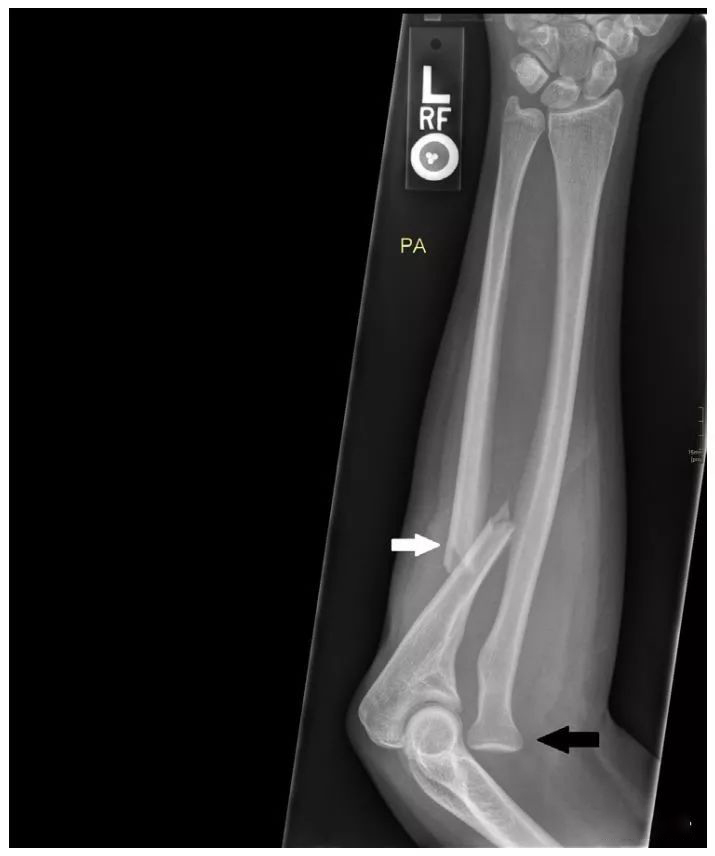

图 二 这名 8 岁女童的前臂侧位片显示桡骨头后脱位 (实心白色箭头) 和尺骨弯曲变形 (空心白色箭头),这与骨骼发育不成熟的患儿的 Monteggia 骨折脱位相一致。这是一种 BadoⅡ 型 Monteggia 骨折脱位。

图二